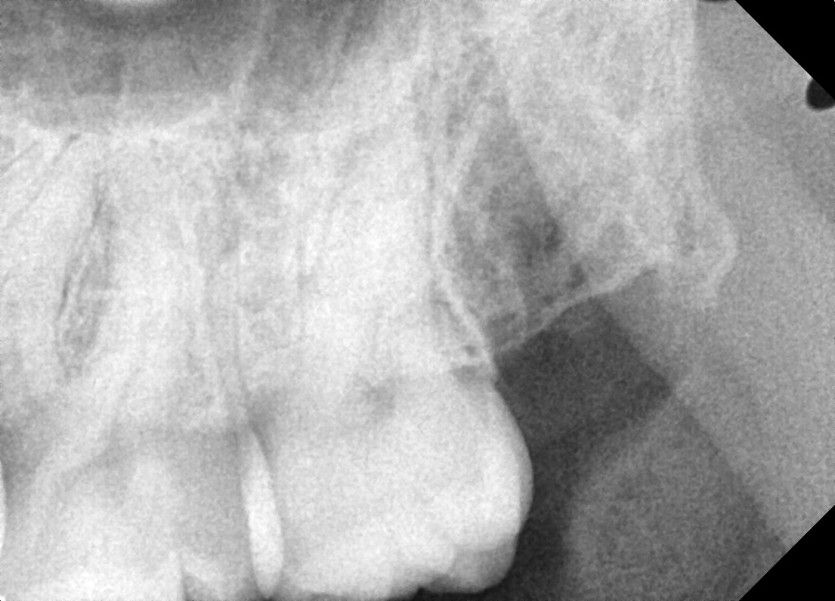

#18,28,48 사랑니 발치

구강 외과 전문의가 당일 발치했습니다.